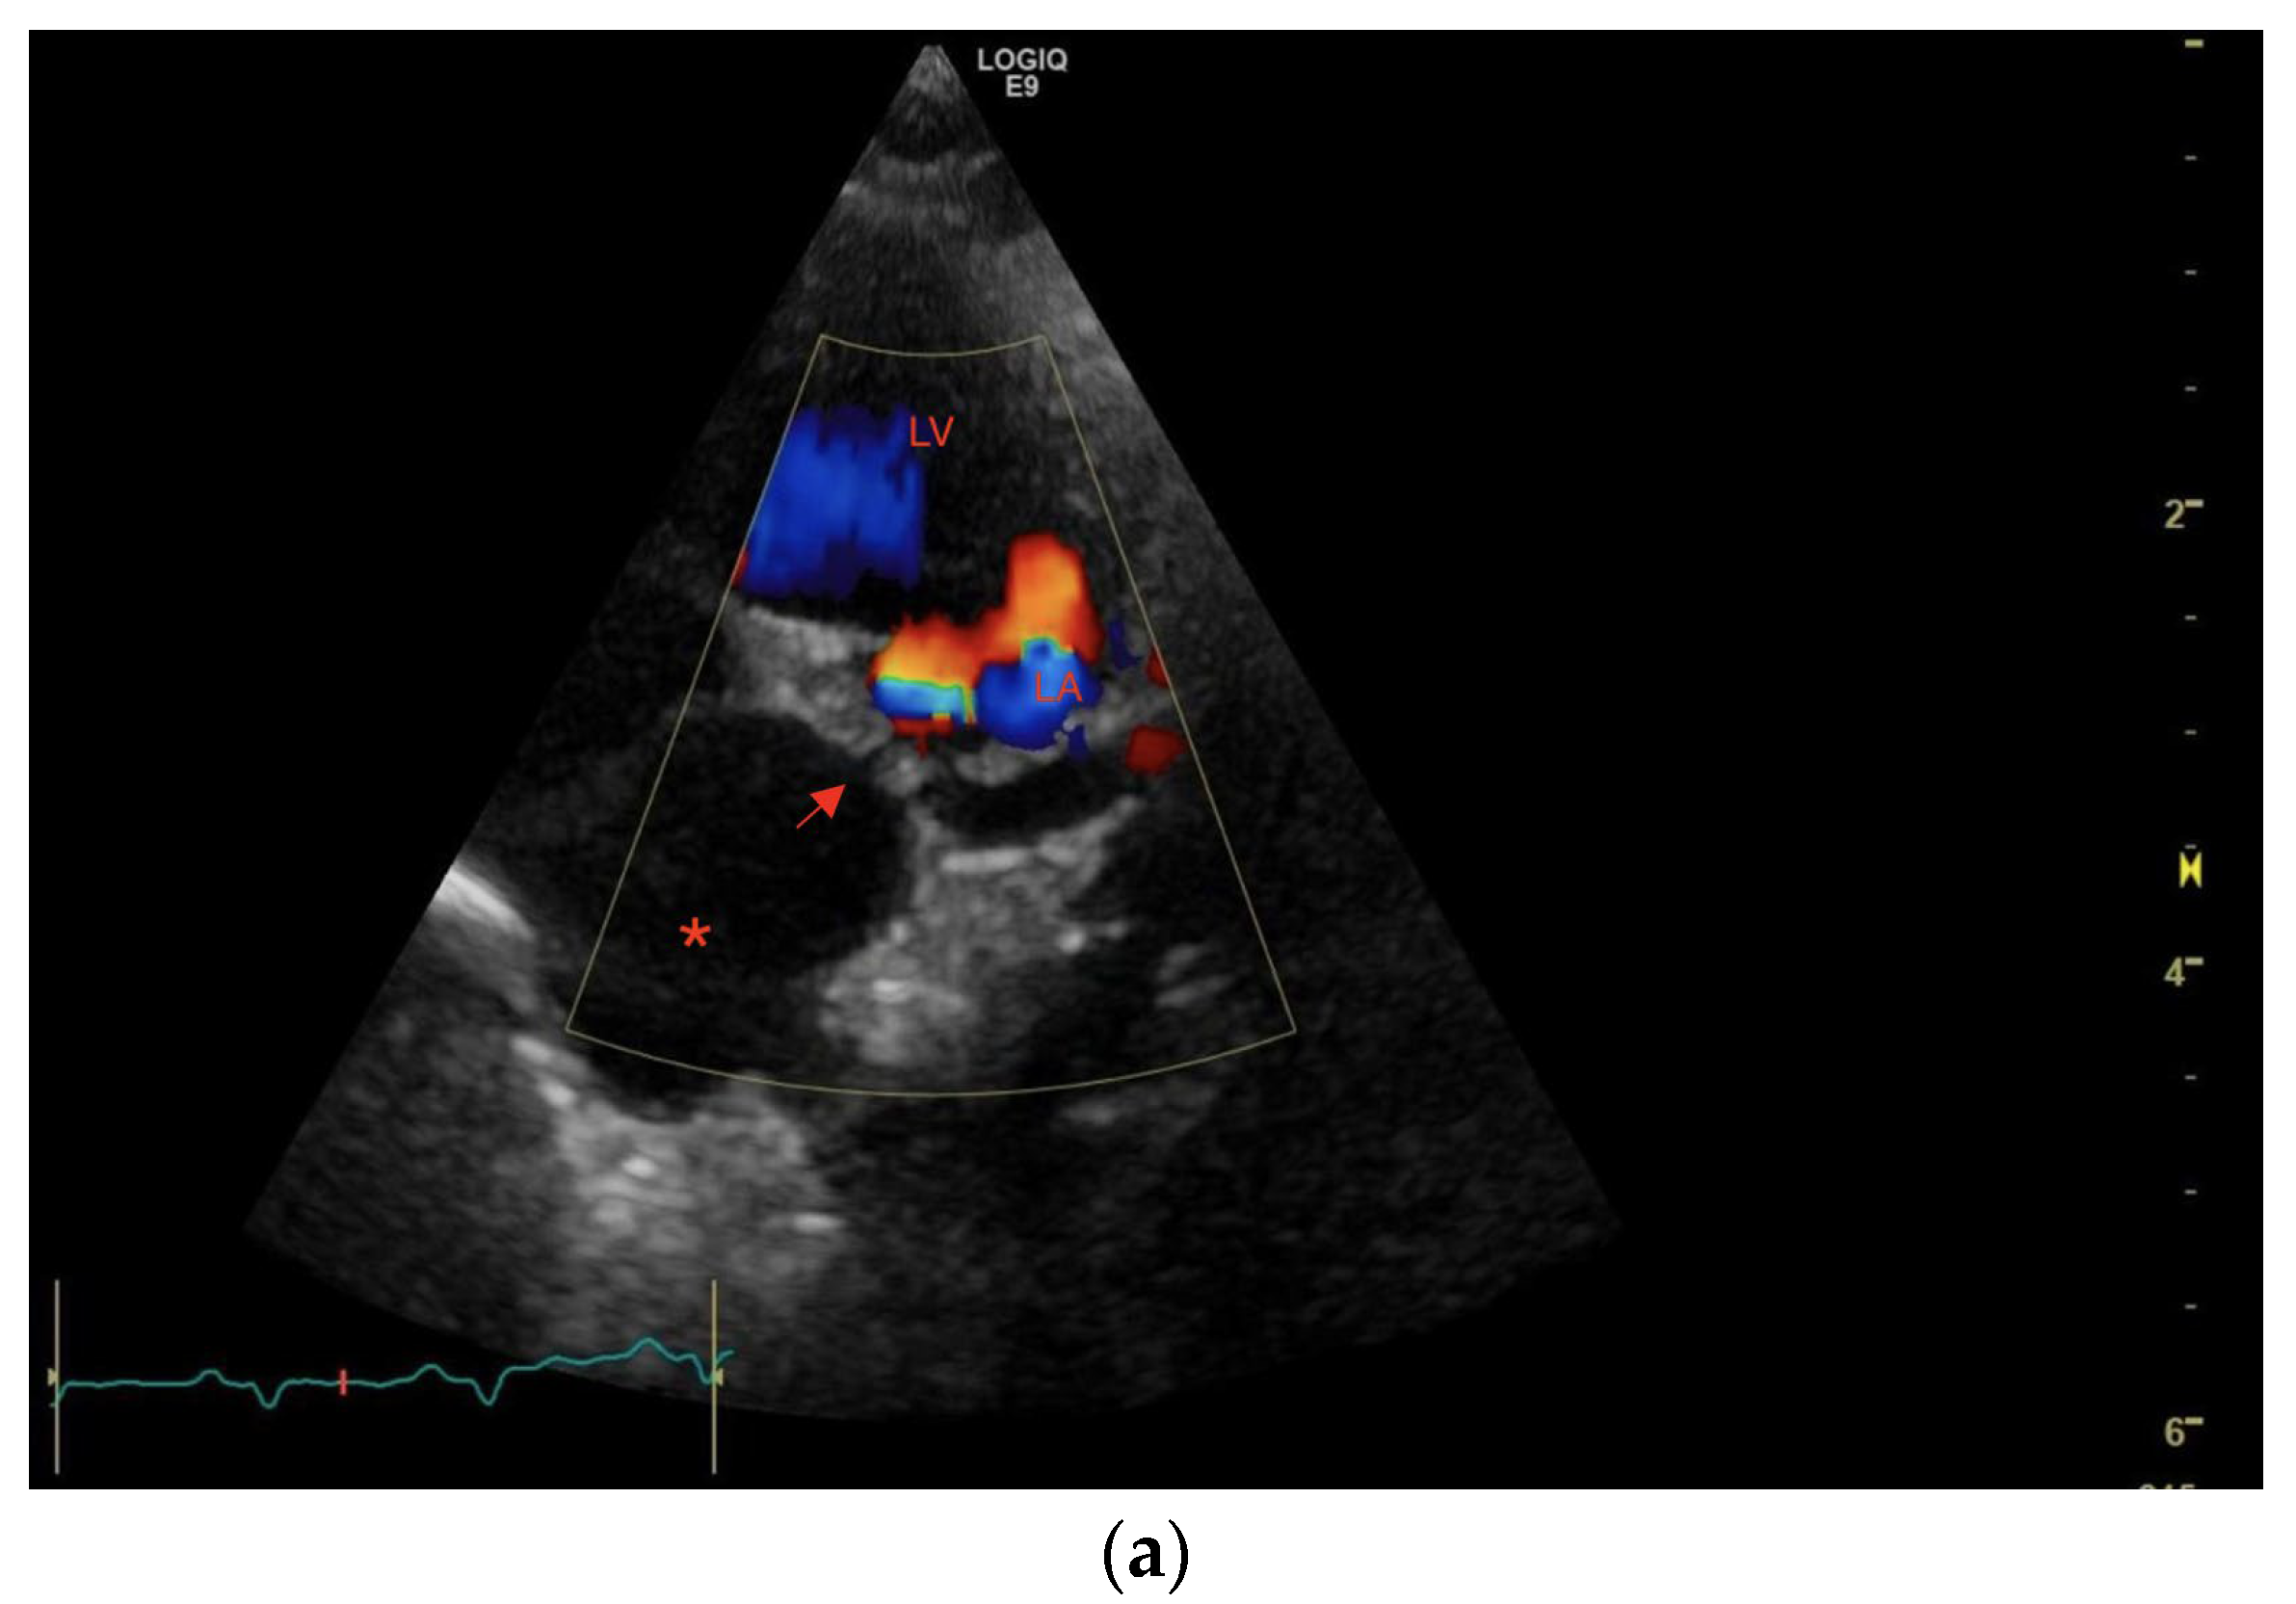

1. Case Description